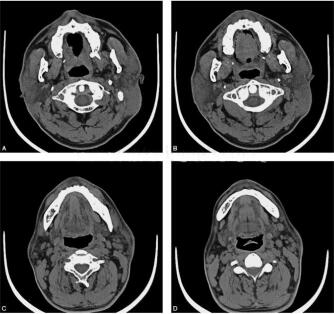

男性患者,52岁,2年来发现双侧耳后肿胀,逐渐增大,未进行系统治疗,近半年肿胀明显,局部皮肤瘙痒,无明显压痛,体表皮温及触觉未见异常,病来听力正常(图1)。

图1 双侧腮腺CT平扫:图A、图B可见双侧腮腺弥漫性增大,密度不均匀增高,边界欠清,局部皮下组织、皮下脂肪消失,邻近皮肤增厚;图C、图D示双侧腮腺周围、颌下周围和颈深部可见多发淋巴结增大,增大的淋巴结密度均匀,边界清楚光滑,无坏死及囊变,几乎不融合

病变发生于头颈部,腮腺是主要好发部位,常表现为:

(1)单侧或双侧腮腺浅叶、面部弥漫性增大,常有多个软组织密度结节,大小不等;

(2)往往累及局部皮下组织,皮下脂肪消失,邻近皮肤增厚,可与腮腺组织界限不清;

(3)腮腺周围、颌下周围和颈深部可见多发淋巴结增大,增大的淋巴结密度均匀,边界清楚光滑,无坏死及囊变,几乎不融合;

(4)受累组织结节密度比正常腮腺组织密度稍高;

(5)增强扫描,肿瘤内部可见均匀或稍不均匀强化,但慢性病例可强化不明显,伴有相应唾液腺的增大。